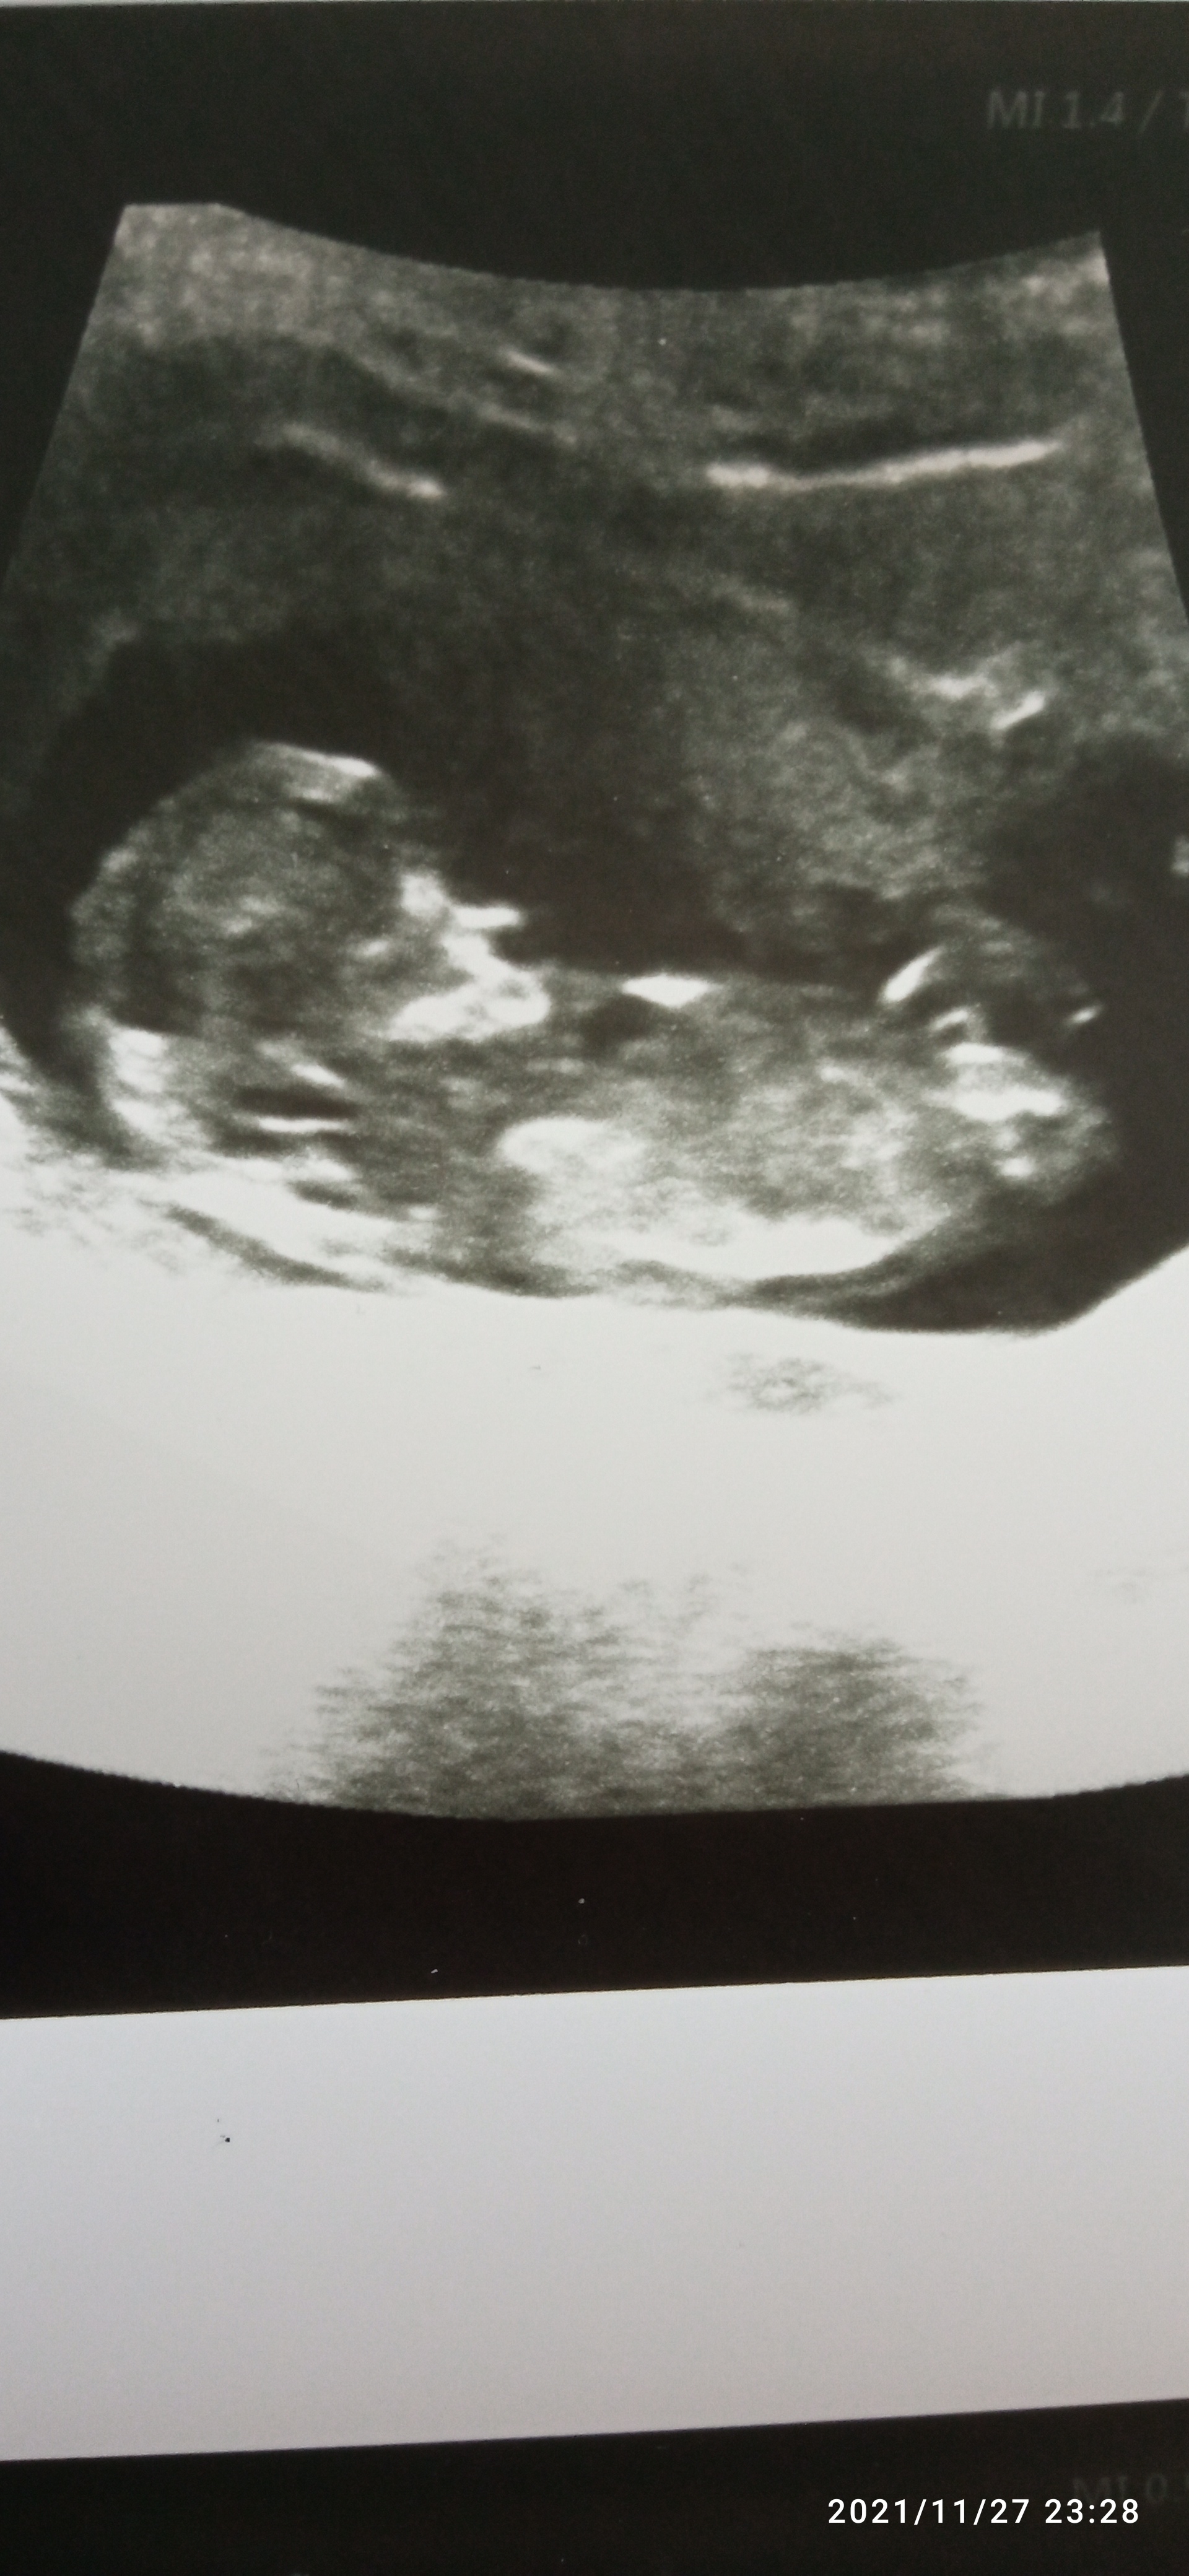

دوستای گلم ویشه حدس بزنین نی نی منچیه امروز ان تی دادم و همه چی سالمه